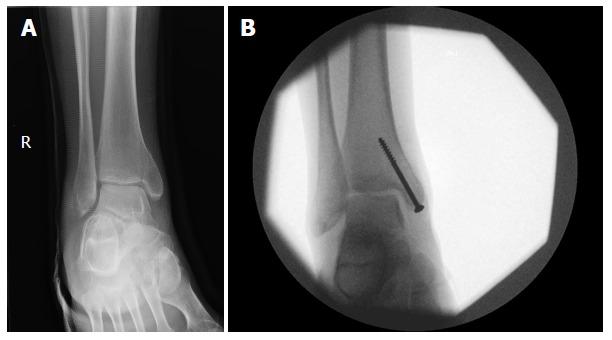

运动中的应力性骨折正变得越来越常见,占所有运动损伤的10%。此类损伤约90%位于下肢。本文旨在确定运动员下肢应力性骨折的最佳管理方法,以提高恢复率并缩短重返运动的时间。这种情况的治疗计划因损伤部位而异。然而,应力性骨折仍明显分为“高”风险和“低”风险。“低风险”应力性骨折是指骨折扩展、延迟愈合或不愈合概率较低的骨折,因此通过休息和限制运动即可可靠地进行处理。这些包括胫骨干后内侧、跖骨干、腓骨远端、股骨颈内侧、股骨干和跟骨的应力性骨折。相比之下,“高风险”应力性骨折的骨折扩展、移位、延迟愈合和不愈合发生率更高,因此需要立即停止活动,并转诊至骨科,以评估是否需要手术干预。这些包括胫骨干前侧、第五跖骨基底、内踝、股骨颈外侧、舟骨和拇趾籽骨的应力性骨折。为了确定管理这些损伤的最佳方法,我们展示并回顾了指导运动员应力性骨折治疗的现有证据。据此,我们注意到某些高风险应力性骨折的手术管理在缩短重返运动时间和提高恢复率方面的作用有所增加。在此之后,针对运动员常见应力性骨折类型的管理提供了关键建议。还给出了五个病例报告,以说明以运动为重点的下肢应力性骨折治疗在临床中的应用。

Recurrent Medial Malleolar Stress Fracture: A Case Report and Discussion of Risk Factors.复发性内踝应力性骨折:一例病例报告及危险因素讨论